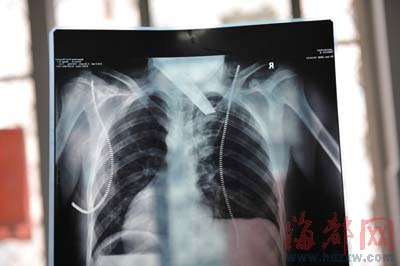

前晚,在第一醫(yī)院急救室,經(jīng)過4個(gè)多小時(shí)的搶救,醫(yī)生將匕首從小勇身上取出,發(fā)現(xiàn)這把匕首的刀尖扎斷了1厘米。由于小勇肺部被刺中,昨天上午,醫(yī)生再次進(jìn)行了3個(gè)多小時(shí)的手術(shù),切除了受傷的部分肺,直到下午,小勇才挺過來!巴α艘灰,現(xiàn)在總算醒了過來。”楊女士一夜沒睡,守在手術(shù)室外7個(gè)多小時(shí),生怕兒子再醒不過來。不過,由于傷勢(shì)嚴(yán)重,小勇目前戴著氧氣呼吸,仍未脫險(xiǎn)。